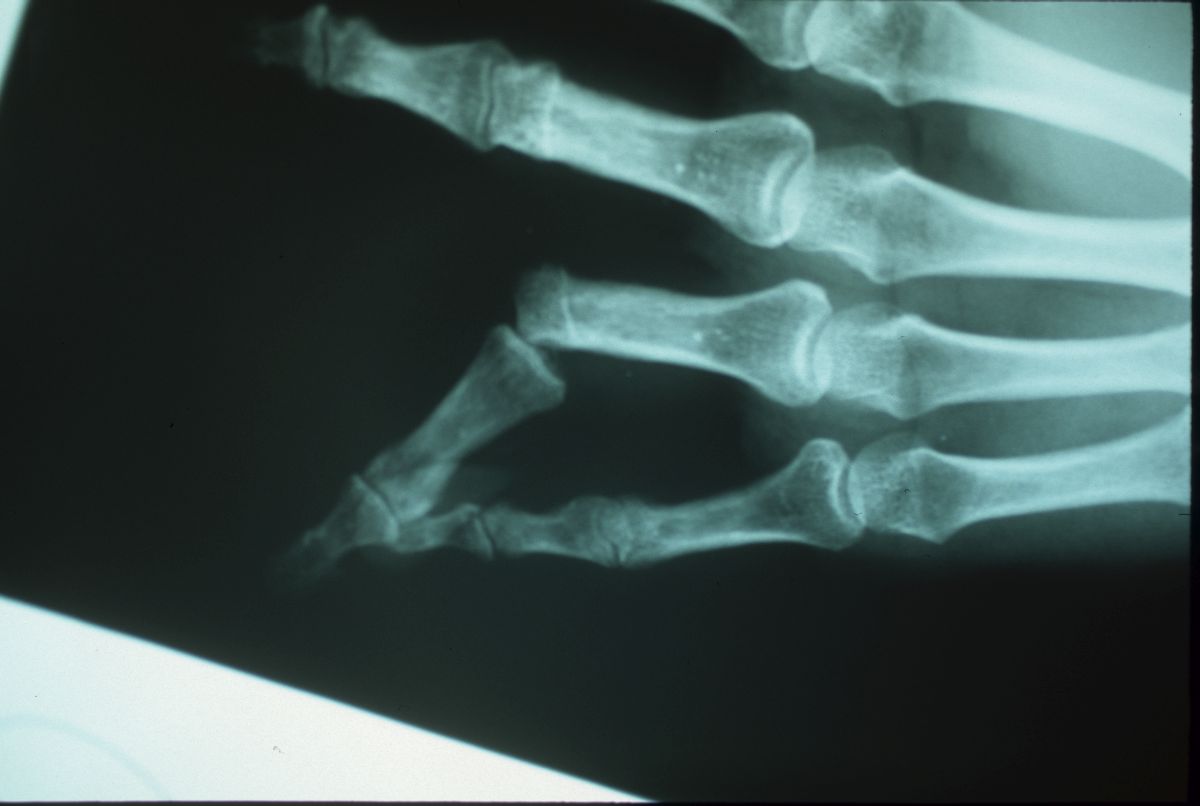

...and a prior left ring finger lateral PIP fracture-dislocation treated with closed reduction: